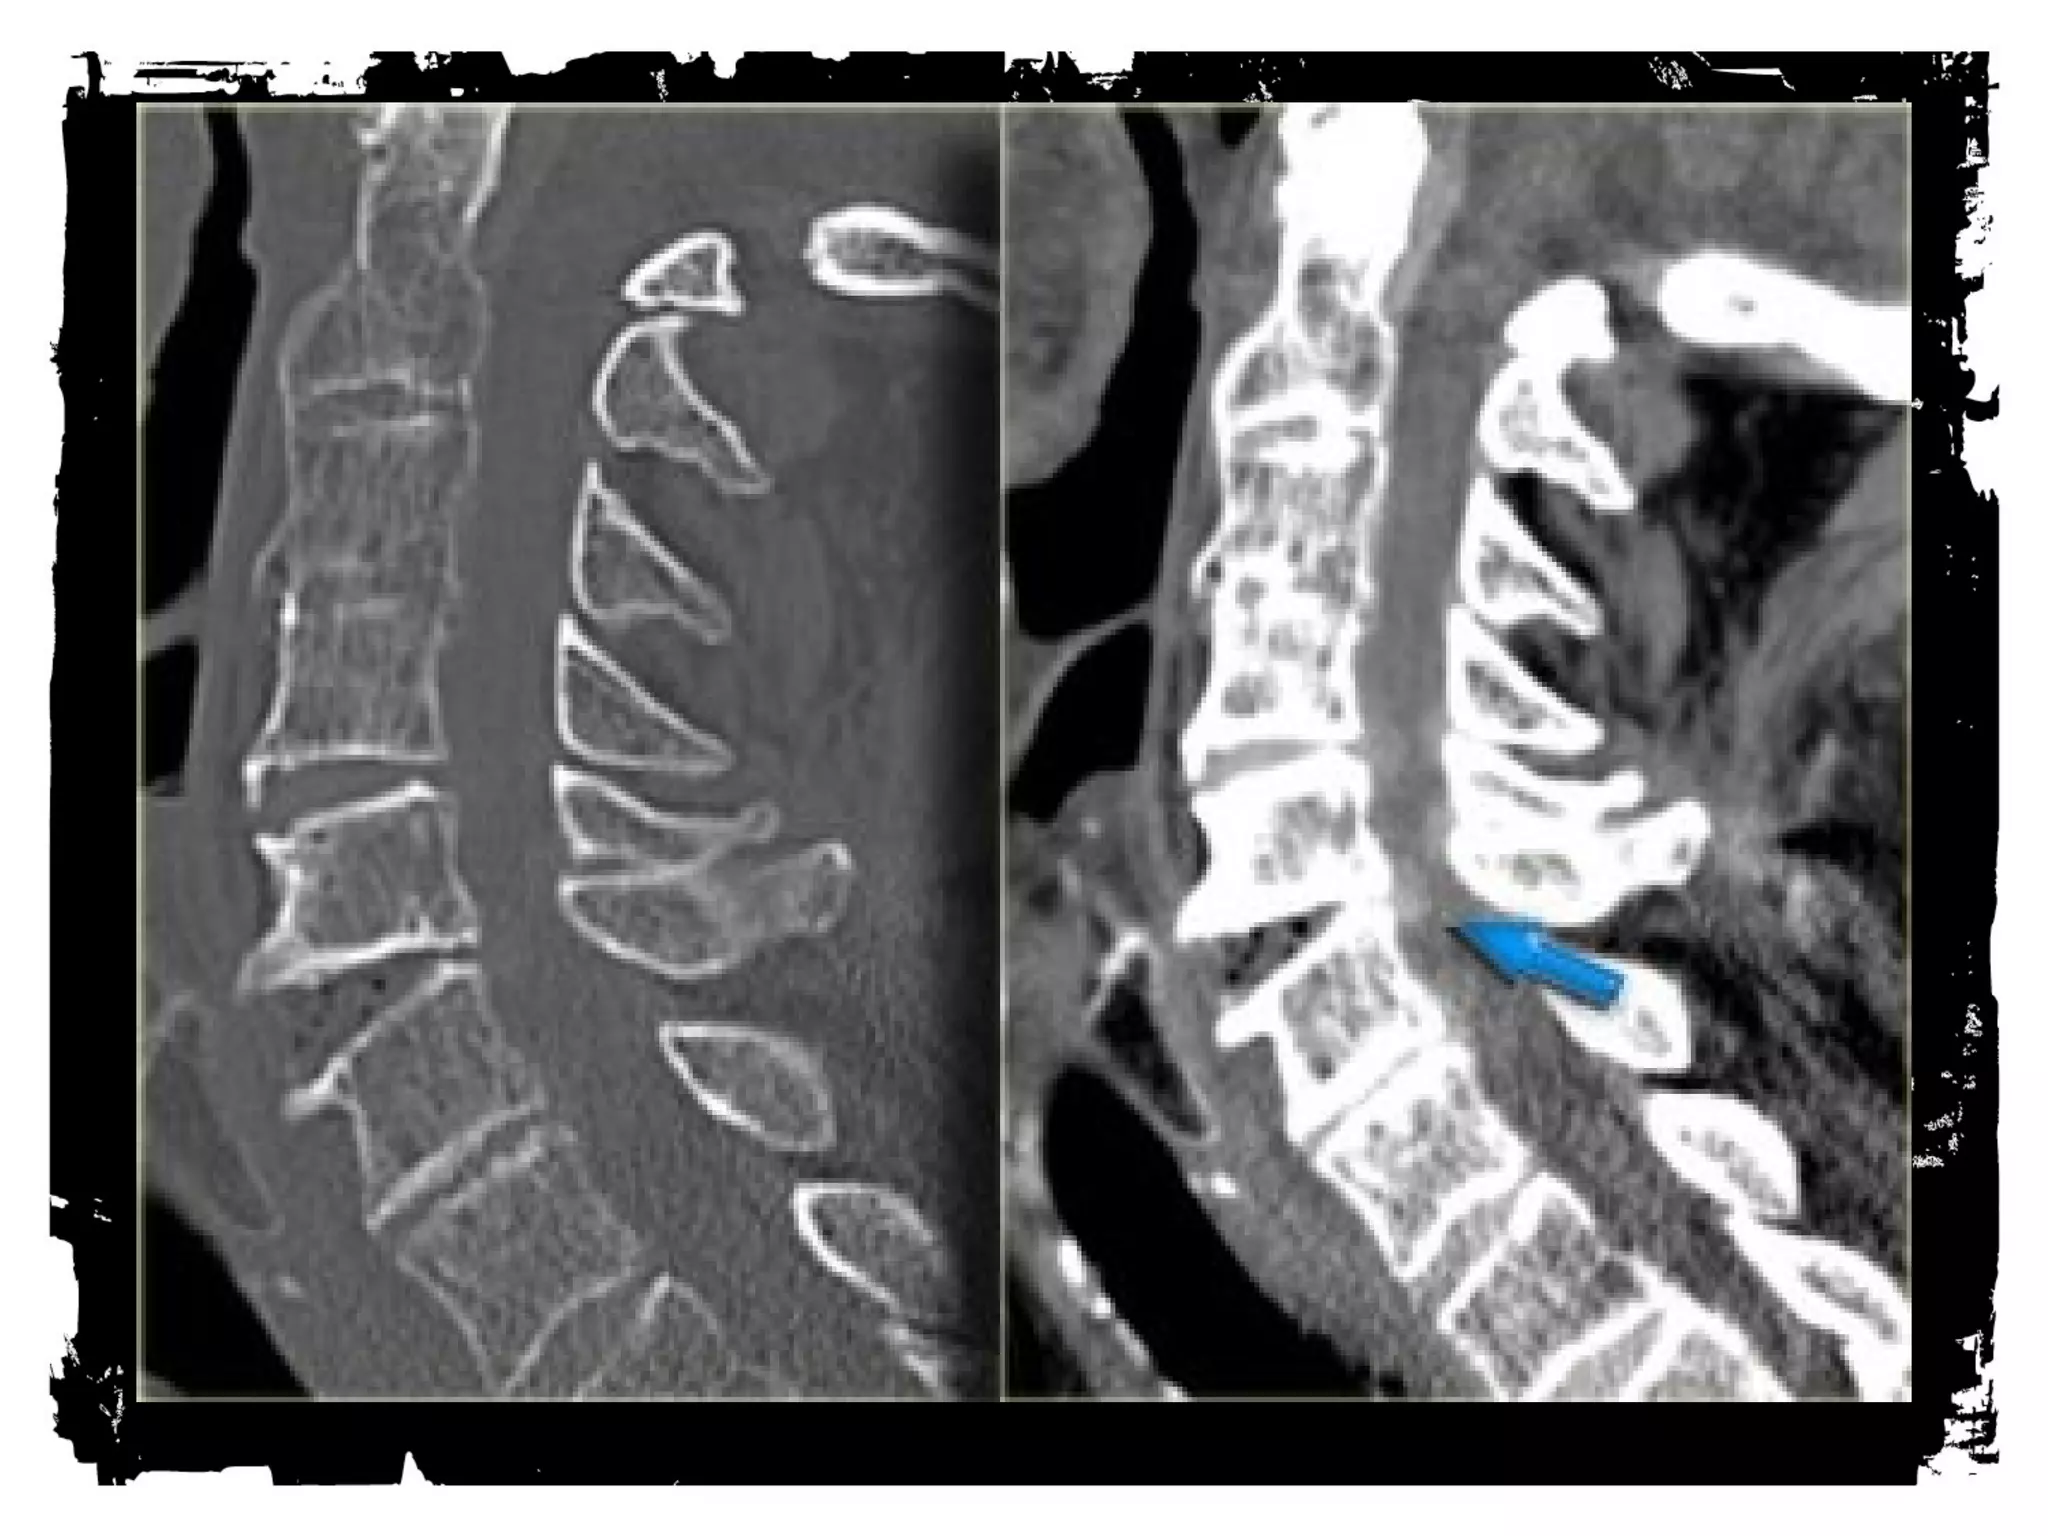

Case (4)

Flexion Tear Drop

Flexion+compression (MVA)

Teardrop fragment comes from the anteroinferior

aspect of the vertebral body

Larger posterior part displaced backward into the

spinal canal

Facets joints and interspinous distances usually

widened, disk space may be narrowed

70% of patients with neurologic injuries

Unstable fracture (complete disruption of ligaments

and anterior cord syndrome

Flexion Tear Drop Flexion+compression (MVA) Teardrop fragment comes from the anteroinferior aspect of the vertebral body Larger posterior part displaced backward into the spinal canal Facets joints and interspinous distances usually widened, disk space may be narrowed 70% of patients with neurologic injuries Unstable fracture (complete disruption of ligaments and anterior cord syndrome

• 112.